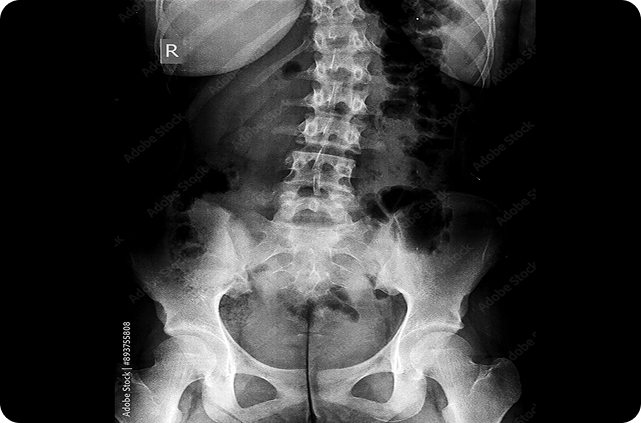

La espondiloartritis axial es una enfermedad inflamatoria crónica del esqueleto axial que termina en nueva formación ósea predominantemente en la columna vertebral y las articulaciones sacroilíacas, llevando a daño estructural progresivo e irreversible, con posterior discapacidad y deterioro de la funcionalidad y la calidad de vida. Se ha reportado que del 10 al 40% de los pacientes con la forma no radiográfica de la espondiloartritis axial progresan a la forma radiográfica en 2-10 años desde el inicio de síntomas. Por lo anterior, la detección y el manejo temprano de la nr-axSpA es esencial para la prevención del daño estructural irreversible, y la progresión a la variante radiográfica. El presente estudio presenta un análisis exploratorio de los cambios radiográficos y la inflamación espinal en pacientes con nr-axSpA activa en manejo con secukinumab durante un período de dos años, proporcionando uno de los conjuntos de datos de imágenes más grandes en pacientes con nr-axSpA disponibles hasta la fecha.

La progresión radiográfica se evaluó usando radiografías convencionales, y el curso de inflamación se evaluó con resonancia magnética de la articulación sacroilíaca y la columna vertebral en el curso de los dos años. Se obtuvieron las radiografías al iniciar el estudio y en la semana 104, las imágenes por resonancia de la columna y las articulaciones sacroilíacas al iniciar el estudio y a las semanas 16, 52, y 104; y se clasificaron utilizando el modified New York scoring system (mNY) para radiografía de la articulación sacroilíaca, el Stoke AS Spine Score (mSASSS) para radiografía de la columna vertebral, el Berlin modification of the AS spine MRI (ASspiMRI) para resonancia magnética de la columna vertebral, y el Berlin Active Inflammatory Lesions Scoring (BAILS) para edema de médula ósea en resonancia magnética de la articulación sacroilíaca. El objetivo del artículo es proporcionar información sobre el efecto en progresión radiográfica e inflamación del tratamiento con secukinumab en pacientes con nr-axSpA.

Un total de 438/555 (78.9%) de los pacientes completaron las 104 semanas del estudio. En general, 50.8% de los pacientes en el grupo de secukinumab con dosis de carga, 47.3% en el grupo de secukinumab sin dosis de carga, y 64% de los pacientes del grupo placebo cambiaron a secukinumab o estándar de tratamiento (sólo 3 pacientes cambiaron a estándar de tratamiento). El estudio encontró que la media de los puntajes basales de sacroileítis (en un rango de 0-8 en el mNY) fue de 1.45 (SD=1.53) en el grupo de secukinumab y de 1.47 (SD=1.60) en el grupo placebo-secukinumab; en la semana 104 los puntajes fueron de 1.41 (SD=1.47) y 1.50 (SD=1.61), en el grupo de secukinumab y secukinumab-placebo respectivamente. En general, 87.7% de los pacientes en el grupo de secukinumab y 85.6% de los pacientes en el grupo placebo-secukinumab mostraron no-progresión en el puntaje mNY para la articulación sacroilíaca a la semana 104 (no-progresión se definió como un aumento en el puntaje de sacroileítis menor o igual al cambio detectable más pequeño, que se situó en 0.46 en un límite de concordancia del 80%).

En cuanto a las radiografías de la columna vertebral, los puntajes basales del mSaSSS fueron de 0.68 (SD=2.35) en el grupo secukinumab y de 0.81 (SD=2.37) en el grupo secukinumab-placebo; a la semana 104, los puntajes fueron de 0.73 (SD=2.49) en el grupo secukinumab, y de 0.88 (SD=2.60) en el grupo secukinumab placebo. En general, 97.5% de los pacientes en el grupo secukinumab, y 97.1% de los pacientes en el grupo secukinumab-placebo mostraron no-progresión estructural a lo largo de los dos años (definida como un cambio en el puntaje mSaSSS menor al cambio detectable más pequeño, que se situó en 0.76 en un límite de concordancia del 80%).